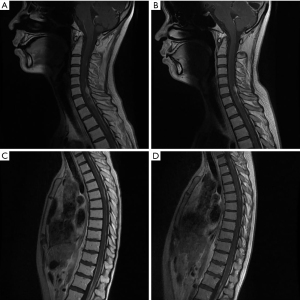

Enhanced MRI of the whole spinal cord revealed 12 MSD cases in total, including 2 cases with intramedullary invasion of the spinal cord. There was 1 case of cervicothoracic MSD and 2 cases of intramedullary invasion of the cervical medulla. Enhanced MRI of the spinal cord showed disseminated lesions of the dotted-line, nodular, and mixed pattern types in 3, 2, and 10 cases, respectively.

After the MSD diagnosis, a part of patients received surgery. 1 patient received total craniospinal radiotherapy, and 2 patients received local radiotherapy to the affected spinal cord segments. Eleven patients received single/2-drug combination chemotherapy or targeted therapy with TMZ, etoposide, carboplatin, cisplatin, irinotecan, sotan, lomustine, teniposide, cyclophosphamide, verofenib, darafenib, bevacizumab, and enduro, 6 patients received intrathecal methotrexate, and 4 patients received symptomatic supportive therapy only. The efficiency of the treatment was little, and we provided representative images of MRI before and after treatment about MSD in GBM (see Figure 1).